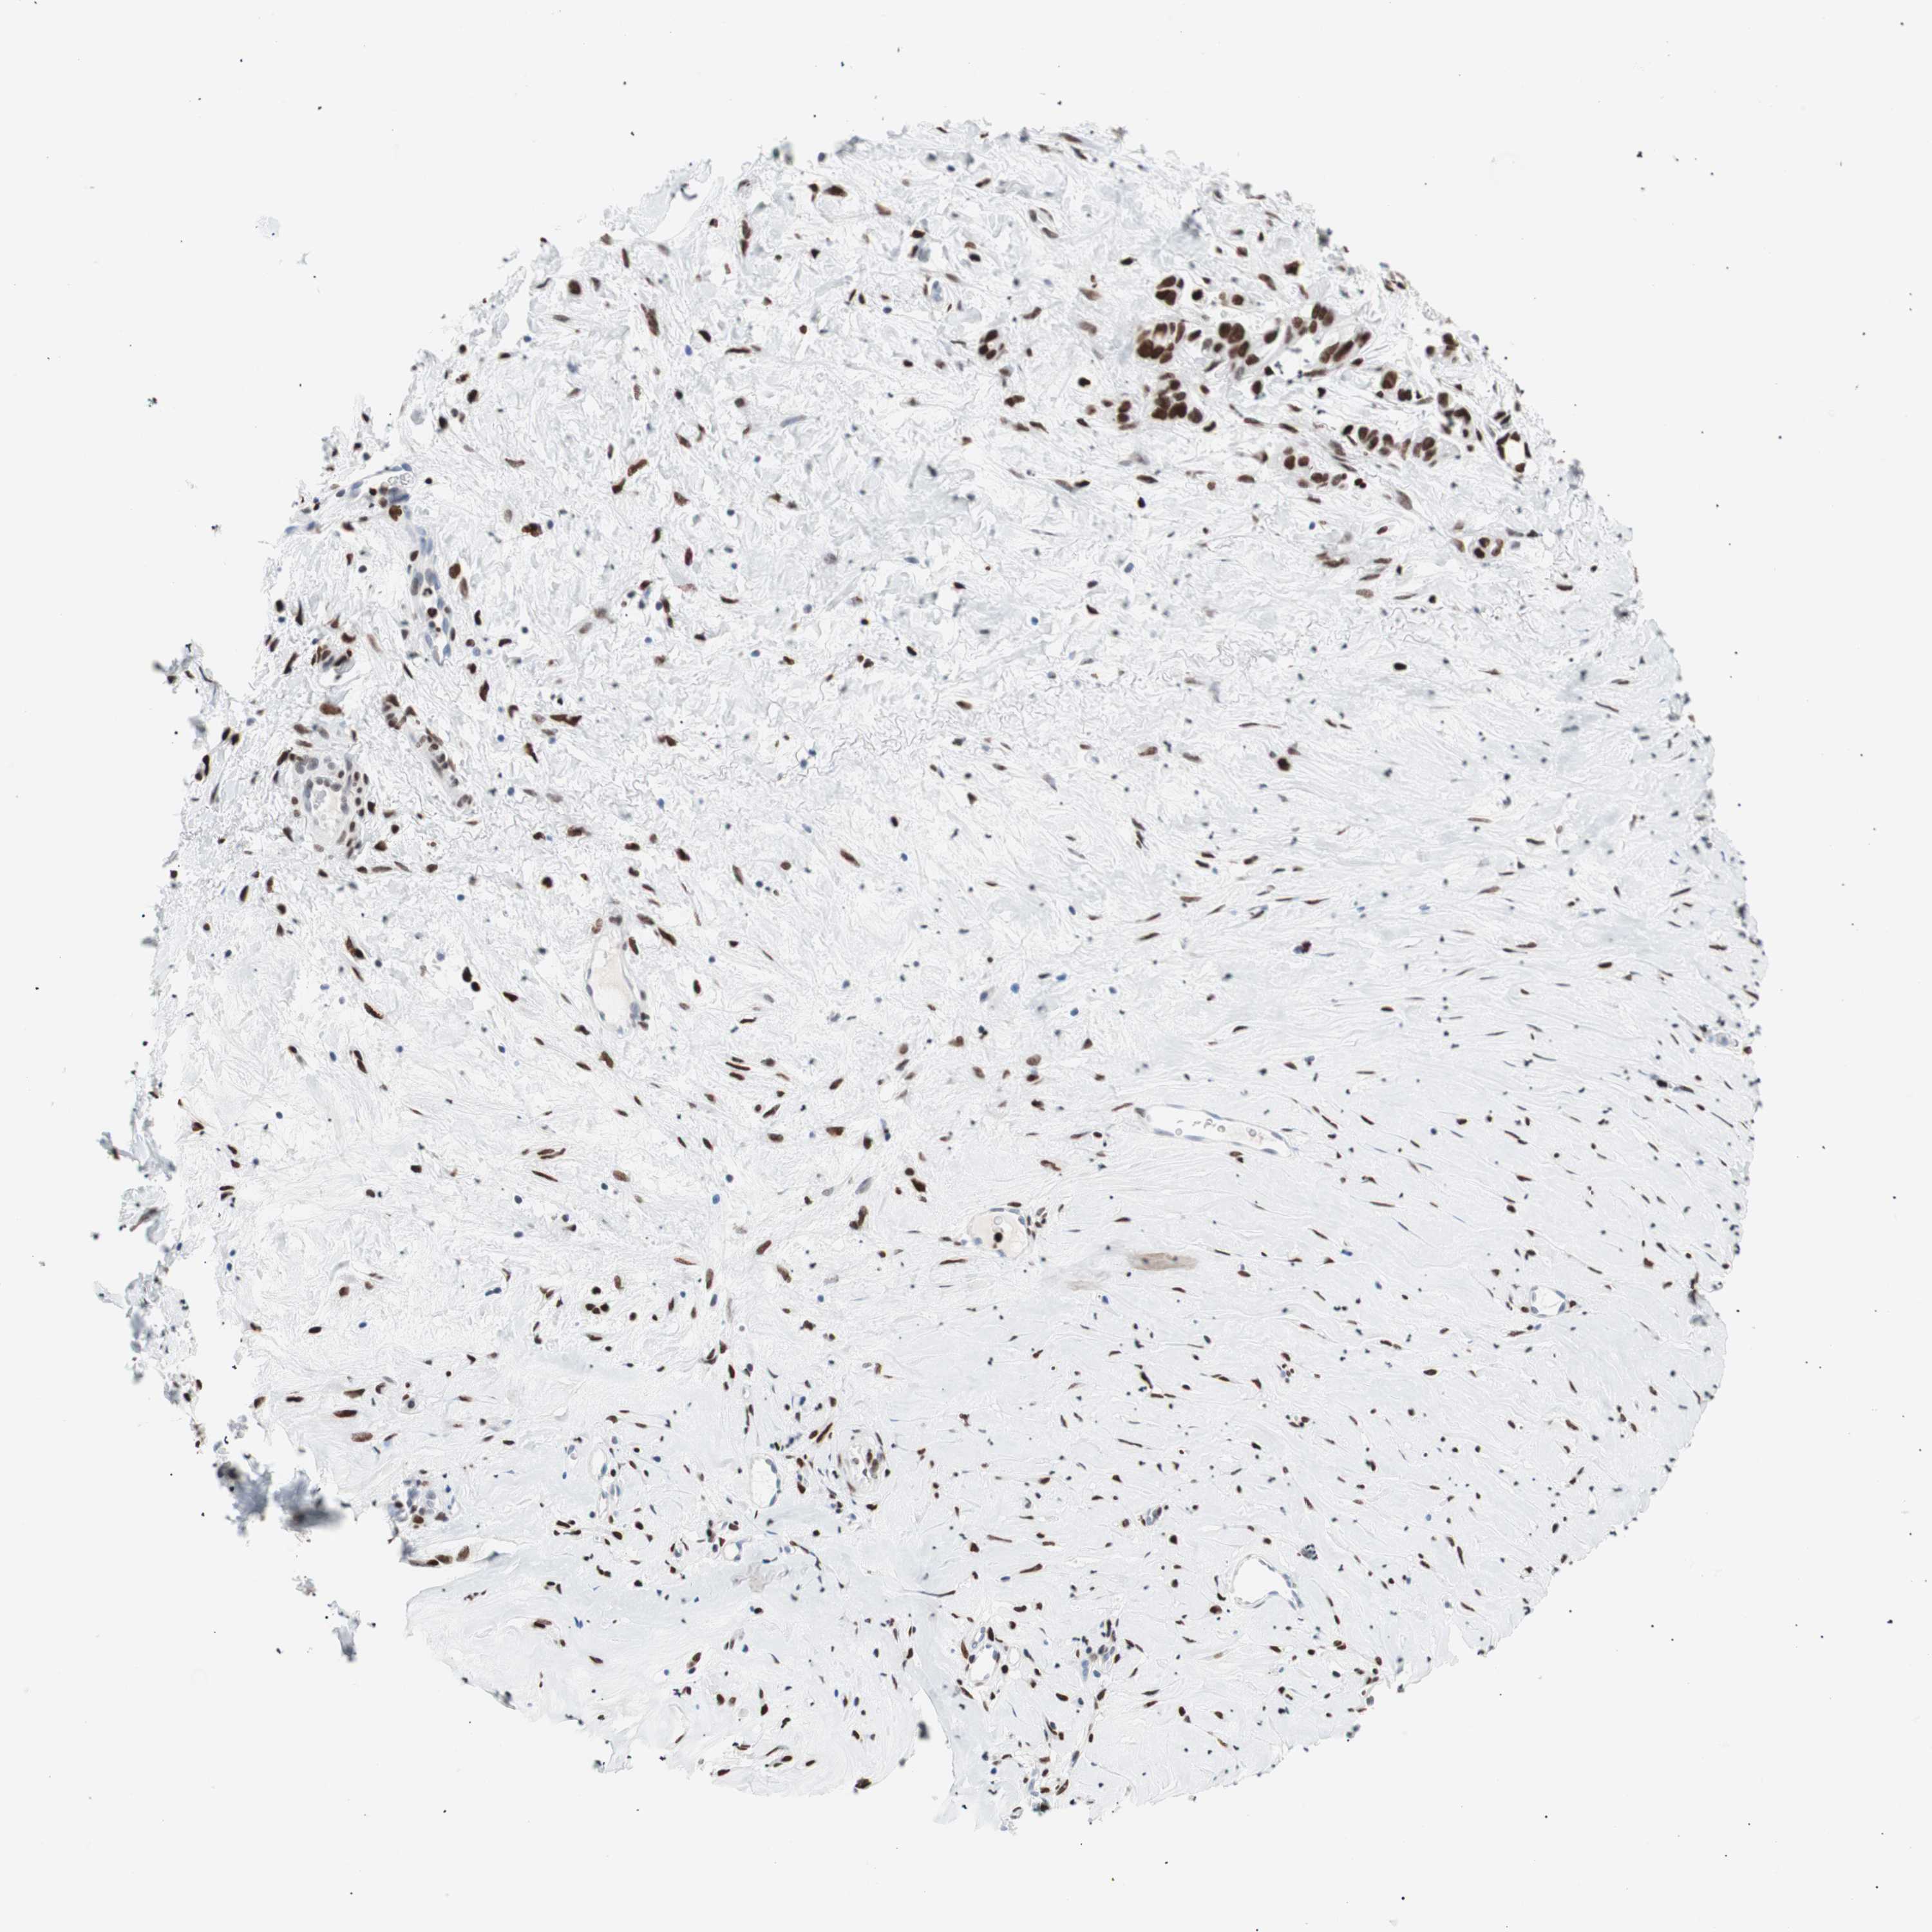

LIVER CANCER - Protein expressioni

A mouse-over function shows sample information and annotation data. Click on an image to view it in a full screen mode. Samples can be filtered based on level of antibody staining by selecting one or several of the following categories: high, medium, low and not detected. The assay and annotation is described here.

Note that samples used for immunohistochemistry by the Human Protein Atlas do not correspond to samples in the TCGA dataset.

Antibody stainingi

Antibody staining in the annotated cell types in the current human tissue is reported as not detected, low, medium, or high, based on conventional immunohistochemistry profiling in selected tissues. This score is based on the combination of the staining intensity and fraction of stained cells.

Each image is clickable and will lead to virtual microscopy that enables deeper exploration of all samples and also displays staining intensity scores, fraction scores and subcellular localization as well as patient and tissue information for each sample.

Antibody CAB004213

Staining

High

Medium

Low

Not detected

Intensity

Strong

Moderate

Weak

Negative

Quantity

>75%

75%-25%

<25%

None

Location

Nuclear

Cytoplasmic/membranous

Cytoplasmic/membranous,nuclear

Cholangiocarcinoma

Carcinoma, Hepatocellular, NOS